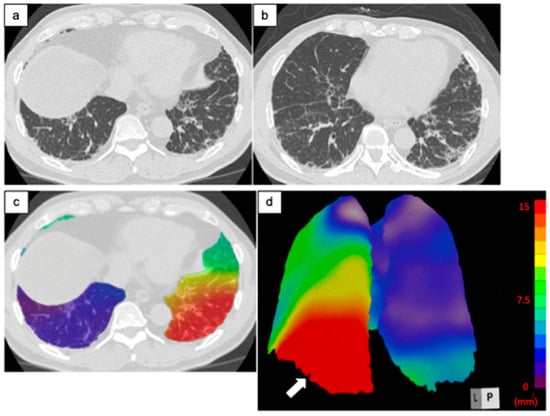

2.3.1. Architectural Distortion Measurement by 3D-AD